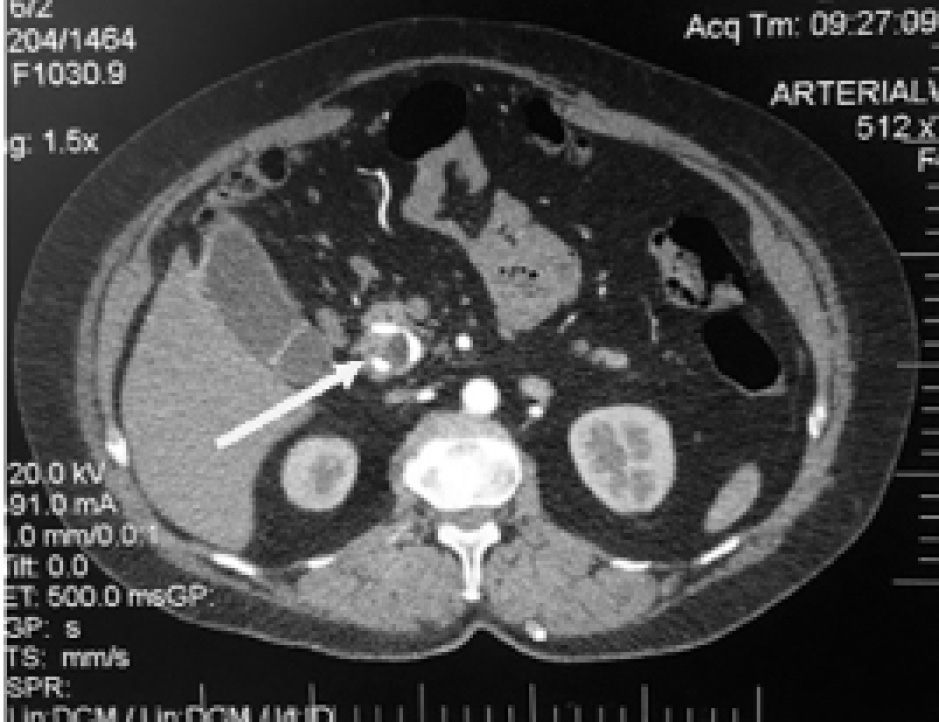

На фоне проводимых мероприятий сохранялись признаки системной воспалительной реакции. По данным компьютерного и ультрасонографического контроля отметили увеличение свободной жидкости в области ПЕА (рис. 7).

Рис. 7. Компьютерная томограмма. А) Свободная жидкость в области ПЕА; Б) Дренирование зоны ПЕА

Учитывая наличие недренирумых отграниченных жидкостных скоплений, выполнено пункционное дренирование под ультрасонографическим контролем на 23-е сут после ГПДР (рис. 8).

Рис. 8. Ультрасонограмма. Отграниченное жидкостное скопление в области ПЕА